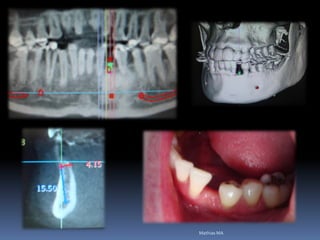

Exames Imaginológicos

Radiografias periapicais, telerradiografias e

panorâmicas;

Tomografias computadorizadas

Softwares de imagens 3D